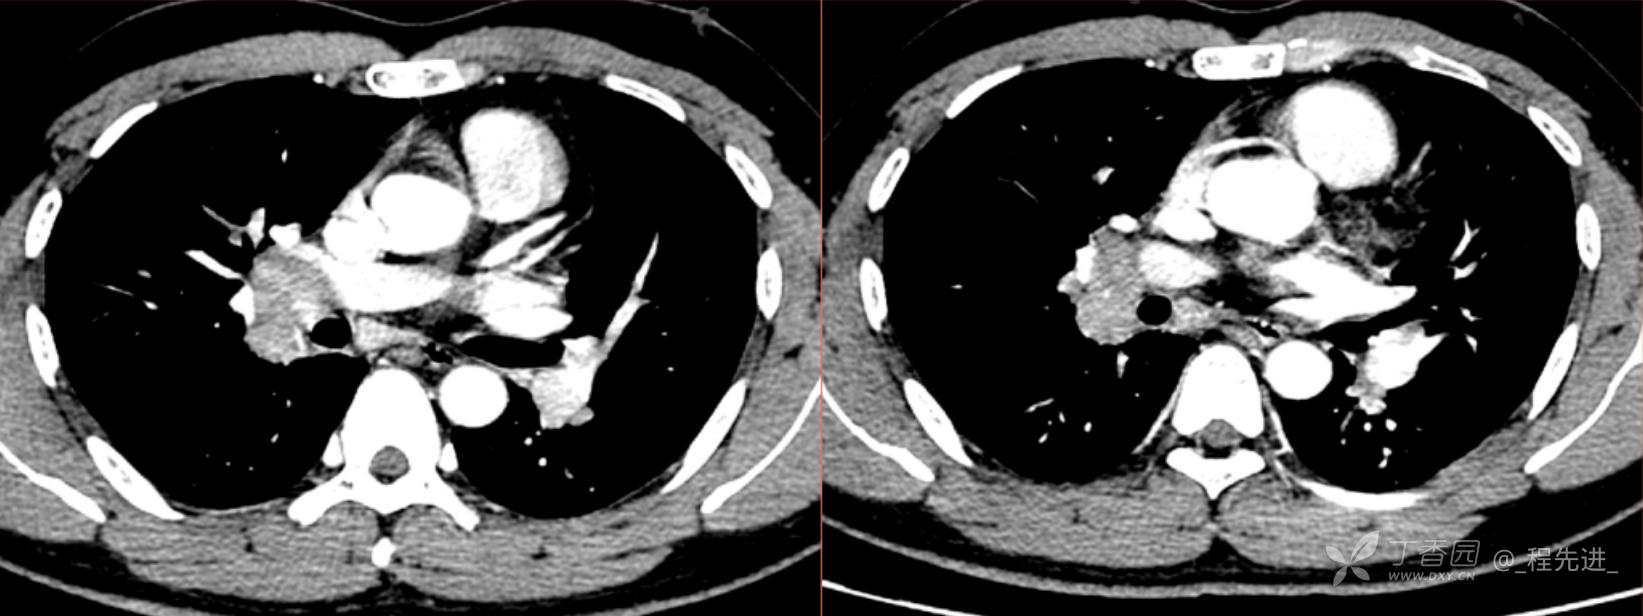

1月特别精彩病例|阵发性刺激性咳嗽,咳少量白色粘液痰1周,期待你的挑战【结果公布】

患者年龄:34岁

简要病史:患者一周前无明显诱因出现阵发性刺激性咳嗽,咳少量白色粘液痰,咳嗽无明显昼夜节律性,无发热、畏冷、寒战,无头痛、胸闷、胸痛,自行服药后 (具体不详) 症状无缓解,3天前当地医院胸片检查示右上病变

辅助检查:肺肿瘤标志物: 神经元特异性烯醇化酶(NSE): 35.72ng/ml(参考值0-16.3);非小细胞肺癌相关抗原211、癌胚抗原、糖类抗原125、铁蛋白、鳞状细胞癌抗原未见异常